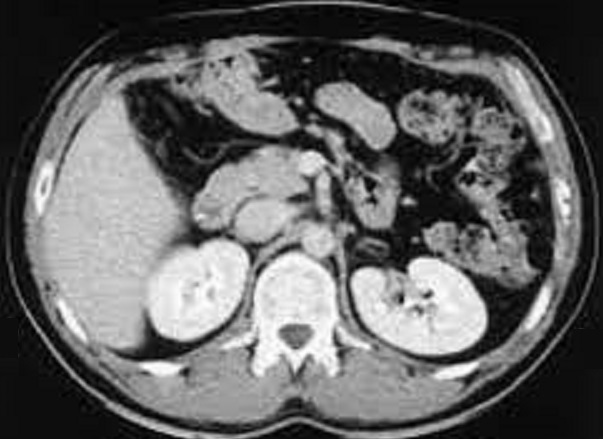

Image

radiologique TDM d'une lymphome pancreatique de la

tete du pancreas avec aspect lesionnel de forme

tumorale hypodense , homogene a mal limitee situe a

la tete du pancreas ( fleche rouge ) . Image TDM en

coupe axiale . |

Aspect lesionel TDM une masse a hypodense

, homogene mal limitee situe du corps pancreas(

fleche rouge . Rehaussement legere du tumeur apres

injection de contrast intraveineuse . Image

radiologique TDM plus contrast intraveineuse , coupe

axiale . |